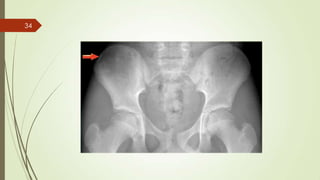

Imaging studies

 X ray : permeative lytic lesion with periosteal reaction.

33

34